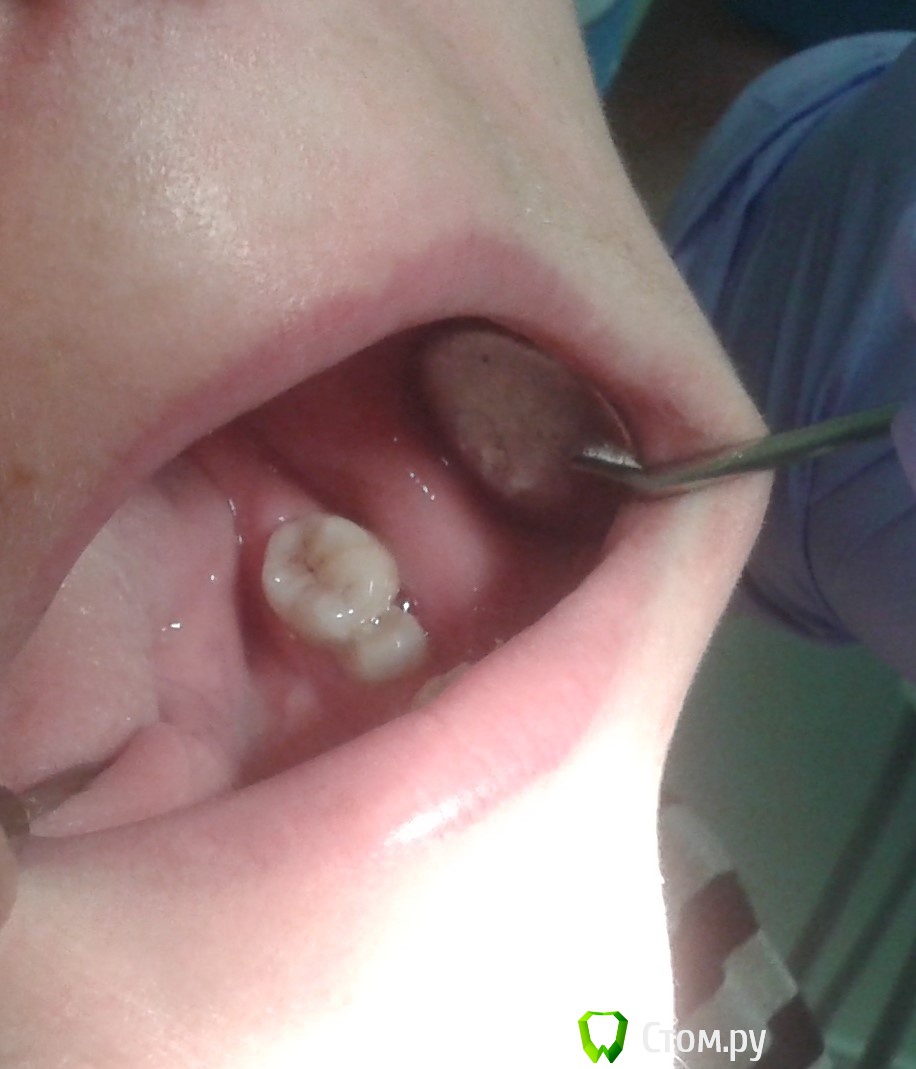

Molo4niy Опубликовано 21 октября, 2014 Поделиться Опубликовано 21 октября, 2014 Пациент,женщина 27 лет.Зубы в таком положении не менее 2-х лет(со слов пациента).Болевые ощущения появились 2 недели назад,перкусия положительная.Подскажите пожалуйста,как лучше поступить.(пациент бюджетный,скорой помощи снять боль и до свидание(((Спасибо. Ссылка на комментарий

Дмитрий Никитюк Опубликовано 22 октября, 2014 Поделиться Опубликовано 22 октября, 2014 Пациент,женщина 27 лет.Зубы в таком положении не менее 2-х лет(со слов пациента).Болевые ощущения появились 2 недели назад,перкусия положительная.Подскажите пожалуйста,как лучше поступить.(пациент бюджетный,скорой помощи снять боль и до свидание(((Спасибо.На вопрос, какие Вам женщины больше нравятся, блондинки или брюнетки, настоящий мужчина ответит - да!На вопрос кем жертвовать в Вашем случае, ответ может быть только один - никем. Сделайте эндо, устранив боль и раздвиньте зубы с помощью ортодонтических сепараторов. Это будет очень бюджетное решение, но в то же время Вы сможете соблюсти главный принцып медицины. 3 Ссылка на комментарий